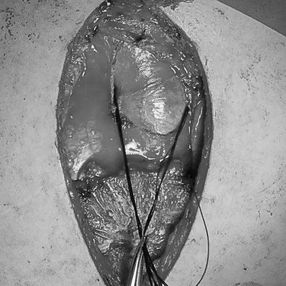

1. An incision was made in the middle of the anterior chest wall to reveal the underlying bone structures.

2. The upper portion of the sternum and the first and second ribs on each sides were excised, revealing that the ascending aorta, aortic arch were closely adjacent to the heart and sternum. Additionally, significant enlargement of the thymus was observed.

3. The thymus was excised and the anterior chest wall was reconstructed using a custom digital material tailored from the patient’s chest data. This ensured a clearance of about 2cm between the chest wall and the ascending aorta.

4. The trachea was confirmed to be free of compression, with the airway pressure reduced from 23 to 12.

5. The digital material was covered with fibrous membranes.

6. Drainage tubes were indwelt and the incisions were sutured.